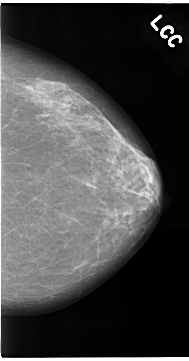

C_0096_1.LEFT_MLO

C_0096_1.LEFT_CC

LEFT_MLO LINES 4704 PIXELS_PER_LINE 2680 BITS_PER_PIXEL 12 RESOLUTION 50 NON_OVERLAY

LEFT_CC LINES 4688 PIXELS_PER_LINE 2456 BITS_PER_PIXEL 12 RESOLUTION 50 NON_OVERLAY